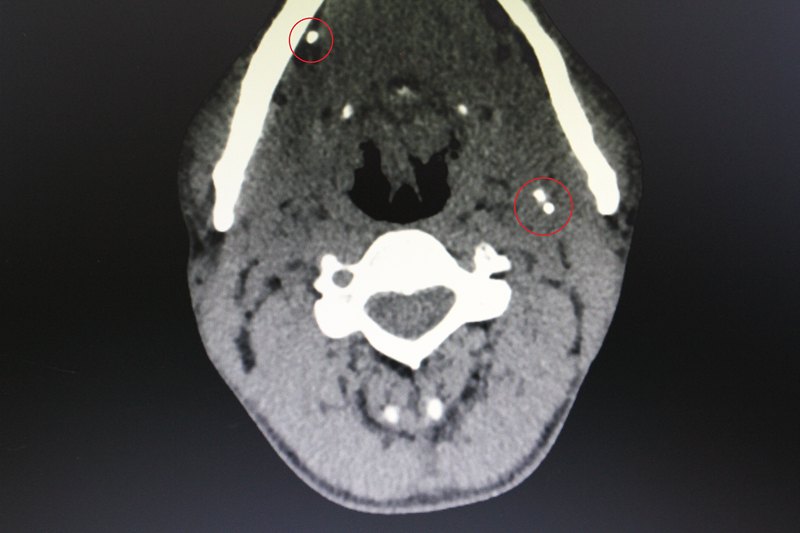

頸部淋巴結(jié)結(jié)核是較常見的肺外結(jié)核感染。淋巴結(jié)結(jié)核按其病程發(fā)展,病理改變可分為4期:1期為結(jié)核性肉芽腫,以增生為主,其內(nèi)無或僅見微小干酪樣壞死;2期淋巴結(jié)發(fā)生壞死,病灶中心見成片無結(jié)構(gòu)的干酪樣壞死物質(zhì),淋巴結(jié)包膜尚完整;3期淋巴結(jié)包膜破壞,合并淋巴結(jié)周圍炎,多個(gè)病灶互相融合粘連;4期干酪樣壞死物質(zhì)液化,穿破至周圍軟組織形成冷膿腫,部分可破潰形成竇道。該病好發(fā)于青少年,且女性多于男性。病程發(fā)展較慢,臨床表現(xiàn)不典型,常以頸部腫塊就診,多不伴有活動(dòng)性肺結(jié)核及全身癥狀。初期查體可捫及一個(gè)或多個(gè)腫大淋巴結(jié),成串,活動(dòng),無癥狀或輕微壓痛,質(zhì)地一般;晚期病變?nèi)诤险尺B,形成大的團(tuán)塊,并向附近的淋巴結(jié)群擴(kuò)散。當(dāng)淋巴結(jié)包膜破壞后與周圍組織粘連時(shí),局部皮膚為暗紅色,皮膚破潰可見竇道形成。 1. CT 頸部淋巴結(jié)結(jié)核多位于中下頸部及頸后三角區(qū),影像學(xué)表現(xiàn)與不同的病理階段相對(duì)應(yīng),各期病理改變可同時(shí)存在。1期表現(xiàn)為腫大淋巴結(jié)與周圍組織分界清晰,增強(qiáng)后呈均勻強(qiáng)化。2期表現(xiàn)為淋巴結(jié)內(nèi)有低密度區(qū),增強(qiáng)后顯示環(huán)狀強(qiáng)化,環(huán)不是特別薄,一般沒有壁結(jié)節(jié)。3期表現(xiàn)為增大的淋巴結(jié)平掃時(shí)密度不均勻,增強(qiáng)后環(huán)狀強(qiáng)化相互融合形成多房樣改變,每個(gè)小房大小比較一致,一般小于1.5 cm。4期表現(xiàn)為融合成團(tuán)的多房樣改變,形態(tài)趨于更不規(guī)則,向皮膚方向蔓延,并與皮膚及周圍組織粘連,晚期可見皮膚破潰形成竇道。少數(shù)病灶內(nèi)可見點(diǎn)狀鈣化。相對(duì)而言,1期的淋巴結(jié)結(jié)核較不具特點(diǎn),其他幾期相對(duì)多見且特征性強(qiáng)??傮w上不管何期的病變,淋巴結(jié)都較?。ǎ?.5 cm),即使在相互融合的情況下,每個(gè)淋巴結(jié)的形態(tài)尚可分辨。結(jié)核性淋巴結(jié)的另一特征是淋巴結(jié)分布不符合特定引流區(qū)域,往往呈多區(qū)域累及。 2. MRI 隨著病程發(fā)展,MRI表現(xiàn)與不同病理改變相對(duì)應(yīng)。較典型的表現(xiàn)為T1WI低信號(hào),T2WI略高信號(hào),增強(qiáng)后呈環(huán)狀或多房樣強(qiáng)化,中心壞死區(qū)無強(qiáng)化。 3. 診斷要點(diǎn) 多見于年輕女性,CT掃描見頸部多個(gè)區(qū)域淋巴結(jié)腫大,大小較為一致,并呈典型的環(huán)形強(qiáng)化,有時(shí)表現(xiàn)為多個(gè)淋巴結(jié)融合成多房樣改變,偶見點(diǎn)狀鈣化。需與頸部轉(zhuǎn)移性淋巴結(jié)、淋巴結(jié)炎等鑒別。轉(zhuǎn)移性淋巴結(jié)常較大,環(huán)形強(qiáng)化時(shí)壁厚薄不均勻,且淋巴結(jié)相互融合少見。淋巴結(jié)炎的影像表現(xiàn)與結(jié)核相仿,但患者常有局部紅腫熱痛表現(xiàn)。

頸部淋巴結(jié)結(jié)核( tuberculous cervical lymphadenitis)多見于兒童和青年人。結(jié)核分枝桿菌大多經(jīng)扁桃體齲齒侵入, 近5%繼發(fā)于肺和支氣管結(jié)核病變, 并在人體抵抗力低下時(shí)發(fā)病。頸淋巴結(jié)結(jié)核發(fā)病率約占肺外結(jié)核病的80%,患者多無結(jié)核病史,早期無結(jié)核中毒癥狀,往往以頸部無痛腫大淋巴結(jié)前來就診。頸淋巴結(jié)結(jié)核病理成分有肉芽腫、干酪壞死、鈣化及纖維化。頸部一側(cè)或兩側(cè)有多個(gè)大小不等的腫大淋巴結(jié), 一般位于胸鎖乳突肌的前、后緣。初期,腫大的淋巴結(jié)較硬,無痛, 可推動(dòng)。病變繼續(xù)發(fā)展,發(fā)生淋巴結(jié)周圍炎, 使淋巴結(jié)與皮膚和周團(tuán)組織發(fā)生粘連,各個(gè)淋巴結(jié)也可相互粘連,融合成團(tuán)形成不易推動(dòng)的結(jié)節(jié)性腫塊。晚期,淋巴結(jié)發(fā)生干酪樣壞死、液化,形成寒性膿腫。膿腫破潰后形成經(jīng)久不愈的竇道或慢性潰瘍。頸淋巴結(jié)結(jié)核為常見病,但其CT表現(xiàn)與其它淋巴結(jié)病變有重疊,常致誤診。頸淋巴結(jié)結(jié)核CT表現(xiàn)為:頸淋巴結(jié)結(jié)核常較小多發(fā),增強(qiáng)環(huán)影內(nèi)緣光滑。病變淋巴結(jié)多偏一側(cè)分布為主,下中部常見。實(shí)質(zhì)部分強(qiáng)化、干酪壞死平掃密度增高;壞死多位于中心,內(nèi)緣相對(duì)光滑;可出現(xiàn)致密銳利結(jié)節(jié)狀鈣化影,但較少。結(jié)核性肉芽腫與干酪性壞死,二者不同比例的組合,構(gòu)成各種CT表現(xiàn)。為減少頸淋巴結(jié)結(jié)核的誤診率,臨床醫(yī)生應(yīng):細(xì)問病史,尤其是結(jié)核接觸史等;對(duì)伴有結(jié)核毒血癥狀的患者,如抗炎治療不理想,除惡性腫瘤外,應(yīng)高度懷疑本??;對(duì)懷疑為頸部淋巴結(jié)結(jié)核的患者,應(yīng)及時(shí)選擇性行頸部彩超、結(jié)核菌素試驗(yàn)、結(jié)核抗體檢測(cè)以及抗酸染色和胸片等檢查,必要時(shí)針刺細(xì)胞學(xué)檢查或淋巴結(jié)活檢??菇Y(jié)核治療對(duì)頸部淋巴結(jié)結(jié)核患者有效,治療時(shí)間一般在1年以上。